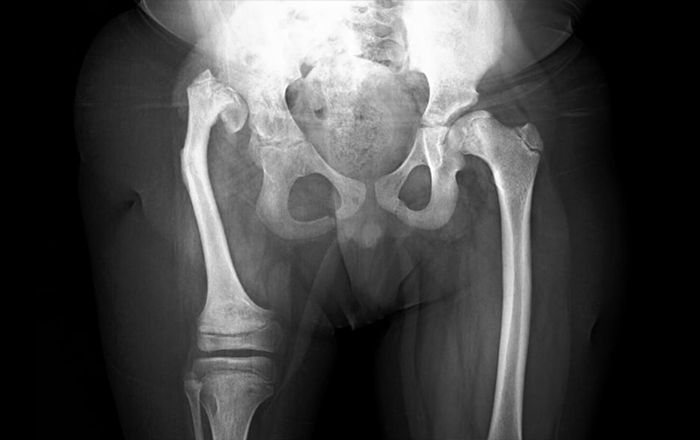

• Kalça çıkığı (Gelişimsel kalça displazisi)

Doğuştan ortopedik bozuklukların teşhisi, genellikle doğum sırasında veya doğum sonrası ilk muayenede yapılır. Teşhis sürecinde aşağıdaki yöntemler kullanılır:

• Radyografi (X-ray)